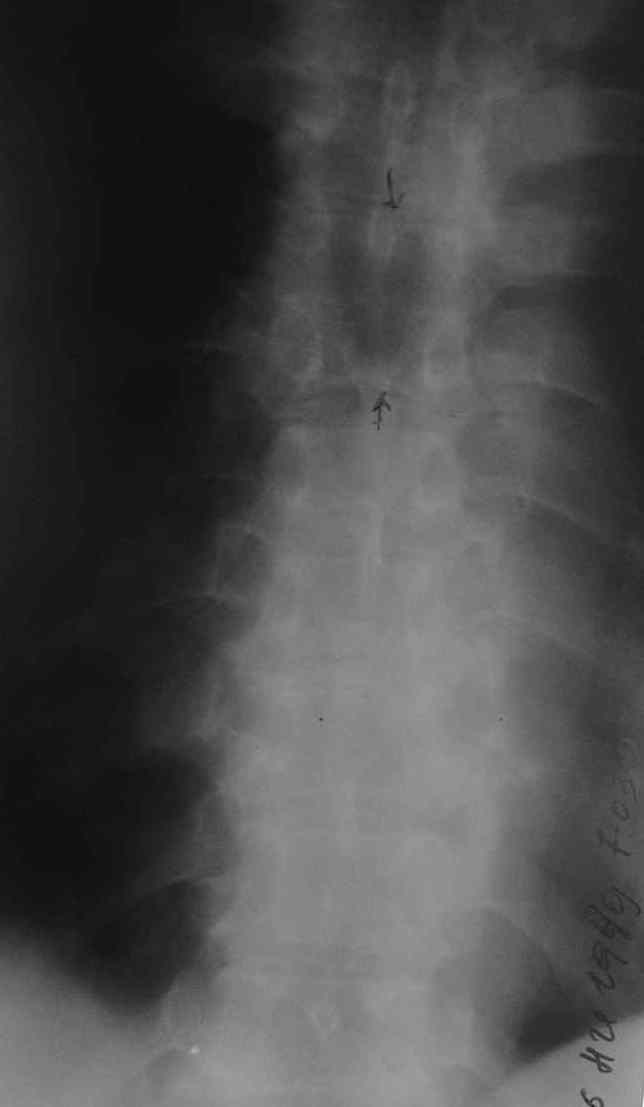

1. Rо-графия грудного и поясничного отделов позвоночника - деструкция с клиновидной деформацией Th5-6. Закл.: застарелый компрессионный перелом? Мт? 2. УЗИ внутренних органов - внутренние органы без патологии. Простата визуализируется с трудом. Края неровные, размеры 6,2х4,8х5,3 см., структура неоднородная. Объем мочевого пузыря - 600,0 мл. Заключение : Хр. б\к холецистит, Аденома простаты. Сч простаты? 3. ФГДС - заключение: Эрозивный дуоденит. Атрофический гастрит. 4. Рентгенография легких - без патологии. 5. Ретроспективный пересмотр флюорограмм за последние 3 года - без патологии. Повторно выполнены клинические и биохимические анализы крови. Заслуживает внимания только нарастание лейкоцитоза (L - 14,0П-4,С-68,Л-64,М-5, СОЭ - 65 мм.\ч). Ликвор: цвет - светло-желтый, ксантохромия- наблюдается, прозрачность - мутная, нейтрофилы - 95%, лимфоциты - 5%, цитоз - 588х106/л, белок - 9,9 промилей. В осадке - I пробирка: L- в большом количестве, Э- неизмененные, в большом количестве,Э- измененные, 1-3 в п\з. II пробирка: L - в небольшом к-ве, Э - неизмененные, 7-10 в п\з, Э- измененные, 2-3 в п\з. К ранее назначенному лечению добавлены инфузионная терапия, антибиотики ( цефтриаксон, ципринол), гормональная терапия (дексаметазон 8,0 мгх2 р\д), гепарин, диуретики, посиндромная терапия. Осмотрен урологом, онкологом. Достоверных данных за наличие Мт. не установлено. В связи с неясностью диагноза, был направлен на КТ в Тираспольскую РКБ. 21 марта больной скончался. На вскрытии - внутренние органы без признаков какой-либо патологии. При разведении волокон передней продольной связки в проекции Th4-6 была вскрыта гнойная полость с наличием деструкции тел указанных позвонков, с прорывом гнойника в позвоночный канал. Дуги и отростки позвонков - без признаков поражения. Гной сливкообразной консистенции, зеленоватого цвета. Гнойных затеков в мягких тканях также не обнаружено.Таким образом, выставлен п\а диагноз: гнойный остеомиелит тел Th4-6 c прорывом в позвоночный канал.

Рентген сделан поздновато,как и КТ.

Судя по представленным рентгенограммам и МР-томограмме (контактная деструкция тел позвонков, натечный абсцесс), анамнезу(медленное развитие заболевания) - нельзя было исключить туберкулезное поражение позвоночника. Собственно об этом забывать в таких случаях нигода нельзя. Так как тогда требуется специфическая противотуберкулезная медикаментозная подготовка.